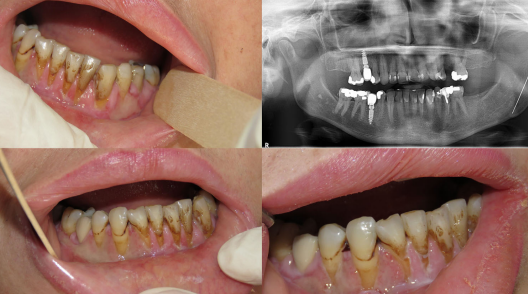

The man was taking metformin and atorvastatin as prescribed but no analgesics, antibiotics, or other medications while taking losartan. He underwent an exam and panoramic x-ray, which showed no visible dental lesions, and his lab work was unremarkable, they wrote.